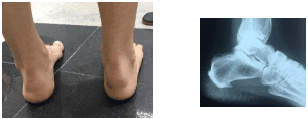

Paciente de 29 anos, com quadro de disúria, inflamação ocular unilateral, dor e aumento de volume em região posterior do calcâneo, de acordo com a imagem abaixo. A principal hipótese diagnóstica é: